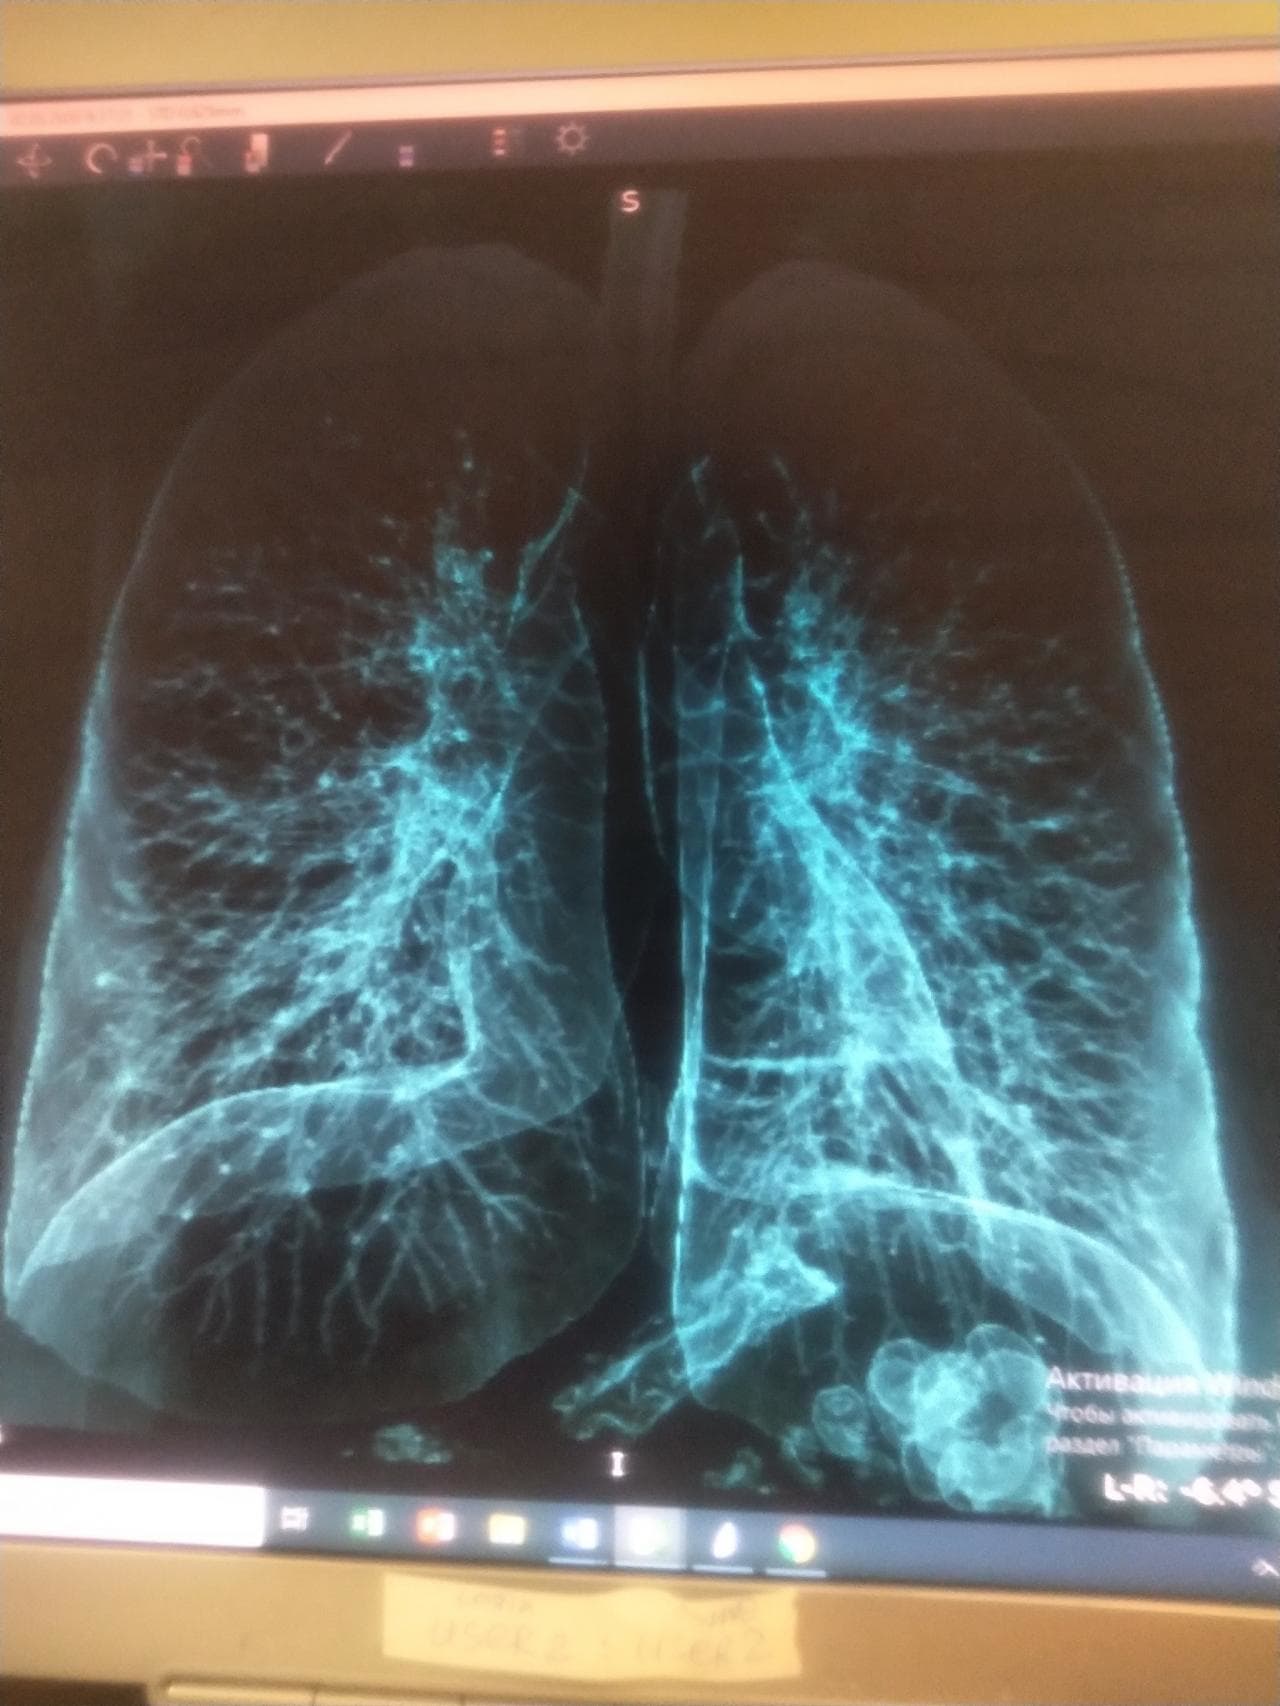

※ コロナ感染者の「肺」(白く広がっている部分は全て炎症)